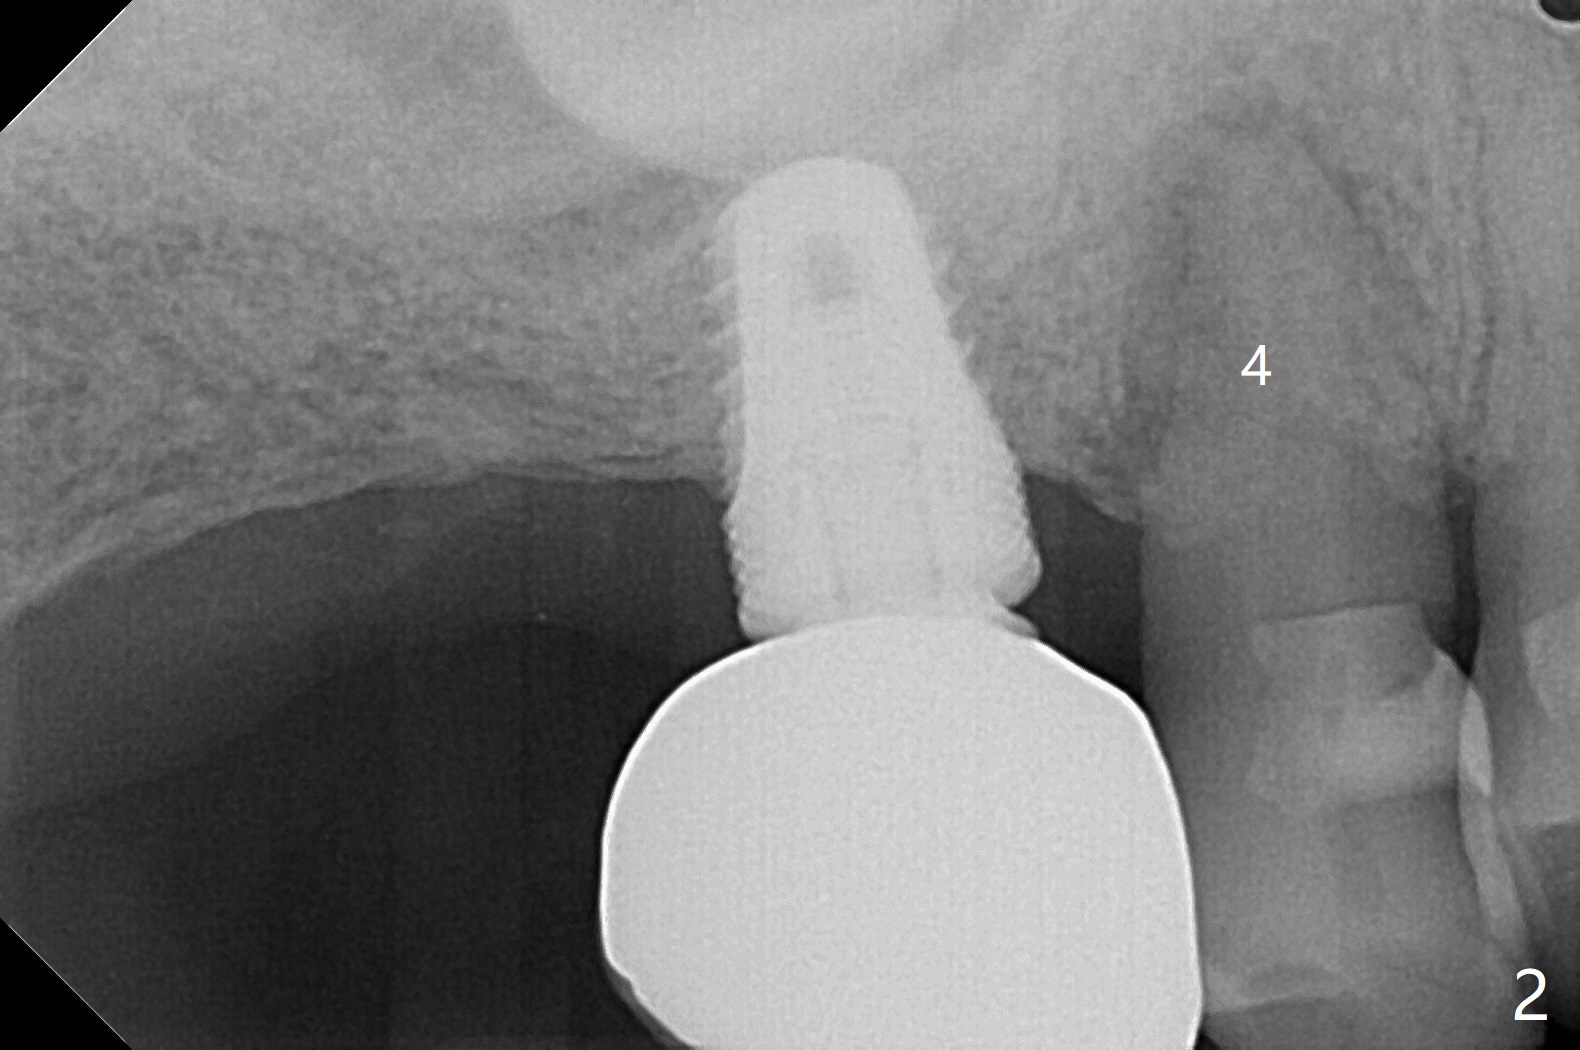

67岁男三年前CT显示4号牙牙周膜增宽(图一),最近咬到米粒中沙子突然松动(图二),要求退休前拔除种植(图三)。